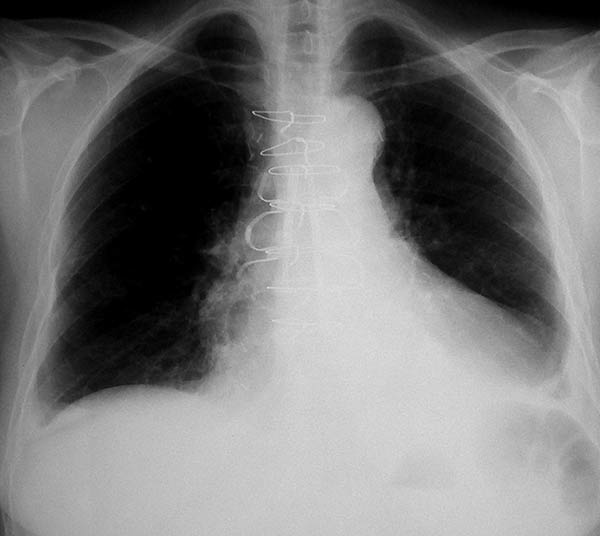

Figure 11. Fourteenth postoperative day image showing sternal wire migration in the caudal sternum segment (*).

Figure 12. Postoperative sternal reconstruction showing sternal fixation with DSS (2 and 3 units in the right and left hemisternum, respectively